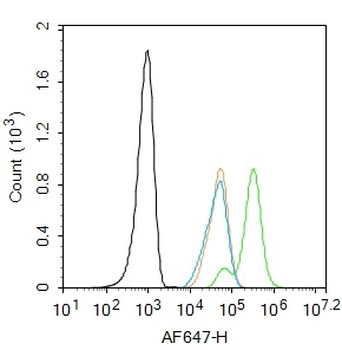

Phospho-Smad3 (Ser423 + Ser425) Rabbit Polyclonal Antibody [orb6983]

FC, IF, IHC-Fr, IHC-P, WB

Bovine, Canine, Equine, Gallus

Human, Mouse, Porcine, Rat

Rabbit

Polyclonal

Unconjugated

100 μl, 200 μl, 50 μlPhospho-SMAD5 (Ser463 + Ser465) Recombinant Rabbit Monoclonal Antibody [orb559123]

50 μl, 100 μlPhospho-Smad3 (Thr179) Rabbit Polyclonal Antibody [orb313112]

FC, ICC, IF, IHC-Fr, IHC-P

Bovine, Canine, Equine, Porcine, Sheep

Human, Mouse, Rat

Rabbit

Polyclonal

Unconjugated

100 μl, 200 μl, 50 μlSMAD7 Rabbit Polyclonal Antibody [orb500819]

100 μl, 200 μl, 50 μlPhospho-Smad3 (Ser213) Rabbit Polyclonal Antibody [orb106193]

FC, IF, IHC-Fr, IHC-P

Bovine, Equine, Gallus, Guinea pig, Rabbit, Sheep

Human, Mouse, Rat

Rabbit

Polyclonal

Unconjugated

50 μl, 100 μl, 200 μl